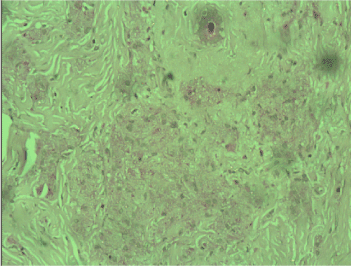

A frozen section was performed during surgery and the result was “invasive tumor, suspicious for malignancy”. Radical left mastectomy was performed with axillary lymph nodes dissection. The histological examination of the symptomatic lesion (11 mm) revealed a tumor, composed of nests of epitheloid tumor cells with monomorphous nuclei with occasional nucleoli, areas with spindle tumor cells in a fibrous background with hyaline change, areas with mature adipocytes. Peripheral nerves were surrounded by tumor nests (Figure 1). Scattered lymphocytic infiltrates were also found. PAS reaction revealed single positive granules in a few tumor cells (Figure 2). The described histological findings are observed in both mammary MFB and granular cell myoblastoma. Immunohistochemical analysis was performed. The tumor cells were positive for: S-100 protein (Figure 3), CD68 (Figure 4), Vimentin (Figure 5). The proliferative index detected with Ki67 is low (1-2%) (Figure 6). The tumor cells were negative for ER, PR and HER. The histological examination of the dissected lymph nodes revealed sinus histiocytosis, follicular hyperplasia and lipomatosis. Metastases were not found.

Figure 1. Peripheral nerves surrounded by nests of tumor cells, Н&E, x10